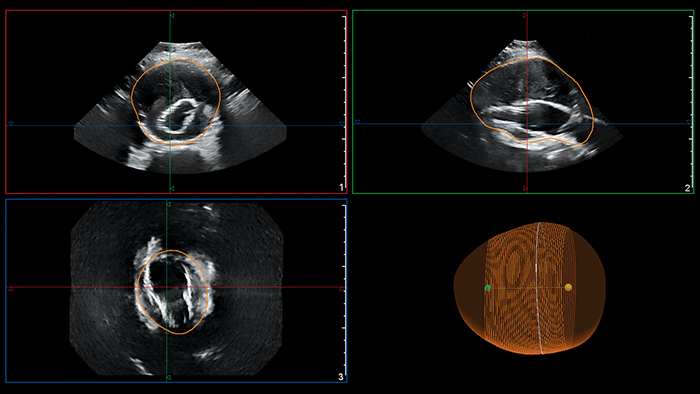

Philips AAA Model segments and quantifies 3D ultrasound data for use in surveillance of native and post-EVAR AAAs.

Philips AAA Model provides key measurements; including the maximum anterior-to-posterior (AP) diameter and partial volume, while also indicating the centerline of the aneurysm.

The maximal diameter of an AAA is ideally measured perpendicular to the centerline, a methodology that so far has only been feasible with 3D CT and magnetic resonance angiography (MRA)5. Philips AAA Model provides the centerline of the AAA throughout the volume of the 3D acquisition, making 3D ultrasound now also feasible with this methodology.